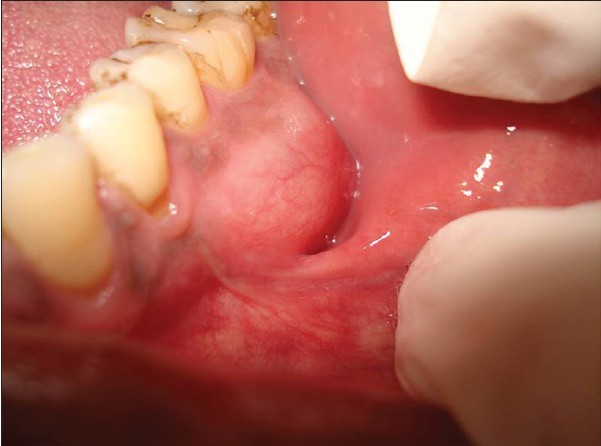

Ameloblastoma is a rare odontogenic tumor, which means it's formed from the normal tissues found in the mouth. Their location is predominately the lower jaw, also known as the mandible. Still, they can be found in the upper jaw or maxilla as well. Sometimes, ameloblastomas are located in the soft tissues surrounding the jaws. There is no known cause for this kind of tumor. However, it may be associated with impacted third molars. Ameloblastomas are usually noncancerous (benign), and they generally affect people between 40 and 60 years old.

Ameloblastoma Symptoms and Diagnosis

Ameloblastoma is usually painless, with the only symptom being swelling in the area. It is usually only identified on radiographic examination in a dental office. Early developing lesions do not displace teeth or cause numbness, so the patient may not know a tumor is growing in one of their jawbones. If a potential lesion is identified on a dental radiograph, more elaborate imaging is required. This will include a CAT scan and possibly an MRI. However, the diagnosis cannot be solely determined by imaging. It requires a biopsy to make the final diagnosis. Cysts will sometimes appear similar to the ameloblastoma on the imaging.